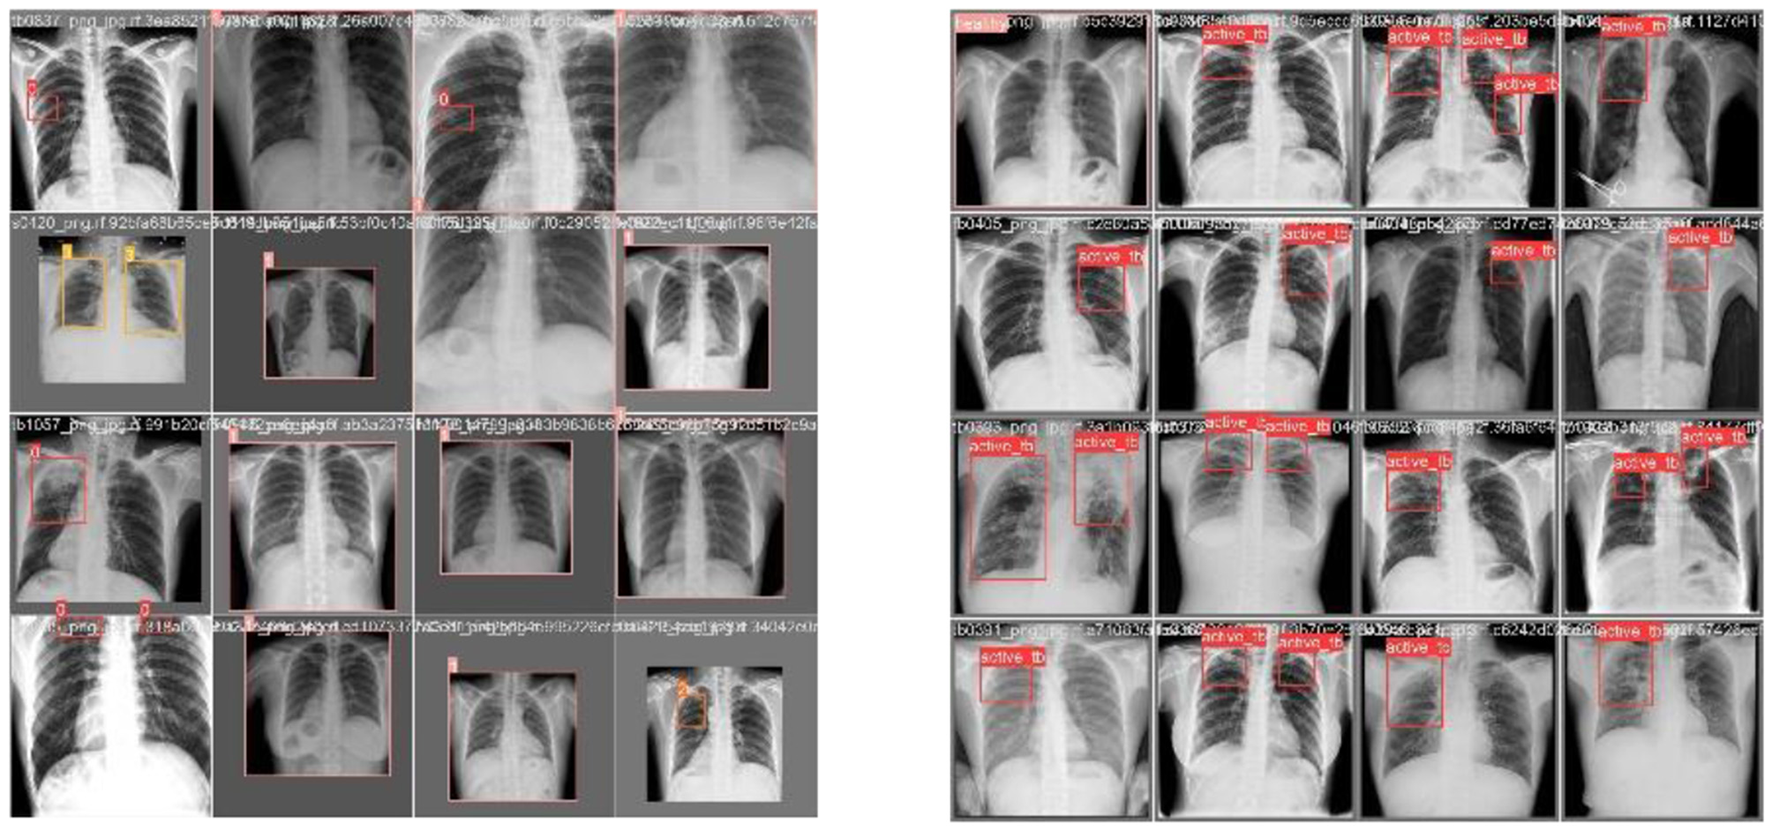

Figure 7

Train batch images.

Figures 7, 8 deliberate the sets of training and validation of image data from the dataset. From Figure 8, the validation set of images shows the level of TB in the lungs; Figure 9 signifies the information about manually labeling objects in the dataset. Here, the red box indicates active TB, salmon pink indicates healthy, the yellow box indicates sick, and the orange box indicates latent TB.

Figure 8

Validation batch images.

Figure 9

Labeling of objects in a dataset.